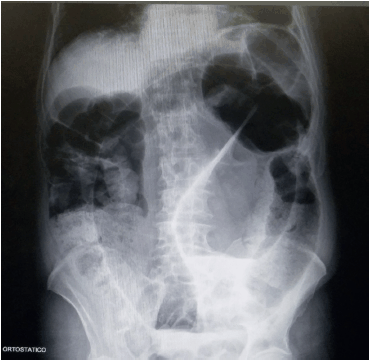

Paciente do sexo feminino, 72 anos, com relato de constipação intestinal prévia, refere início agudo de dor abdominal há 1 dia com parada de eliminação de flatos e fezes. Se apresenta em regular estado geral, sem alteração nos sinais vitais, afebril, abdome distendido, timpânico, sem sinais de irritação peritoneal. Toque retal sem alterações com ausência de fezes ou sangue. Realizado radiografia de abdome em ortostase abaixo (Figura). Sobre a conduta inicial desse paciente, assinale a alternativa correta:

Figura. Radiografia de abdome em ortostase